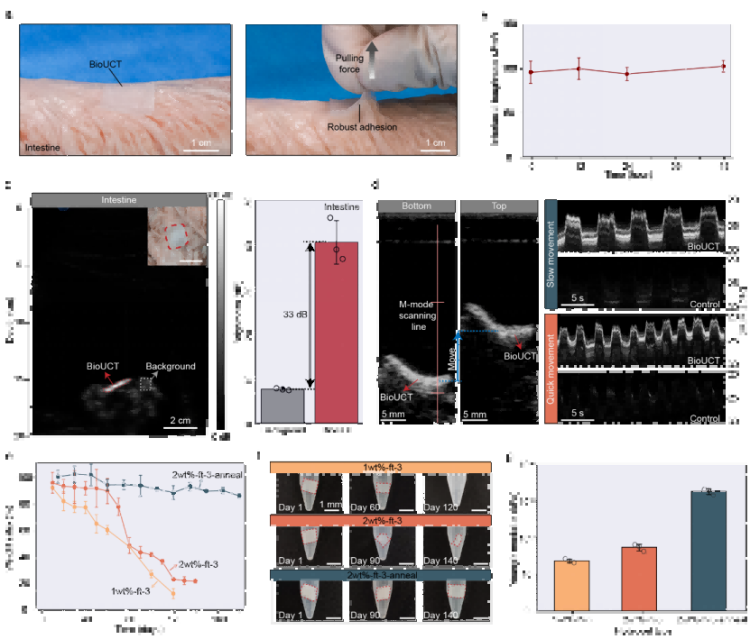

② 智能生物適配:像“第二層生物表皮”一樣工作強(qiáng)力粘附與抗脫落(圖3a-b)離體豬腸實(shí)驗(yàn)證實(shí),BioUCT與腸壁界面韌性達(dá)200 J/m2(相當(dāng)于外科縫合強(qiáng)度),48小時(shí)內(nèi)粘附穩(wěn)定性>95%(圖3b)。拉力測(cè)試中可承受10N以上牽拉(圖3a),遠(yuǎn)超腸道蠕動(dòng)產(chǎn)生的生理應(yīng)力(通常<2N)。

精準(zhǔn)降解調(diào)控(圖3e-g)通過調(diào)節(jié)PVA/CMC水凝膠結(jié)晶度,實(shí)現(xiàn)10%-90%的可控降解速率(120天內(nèi)),且降解過程中楊氏模量保持15-35kPa(圖3g),始終匹配軟組織力學(xué)特性,避免器官損傷。

圖3. BioUCT的離體展示。

③ 離體驗(yàn)證臨床價(jià)值:動(dòng)態(tài)追蹤不再是難題顯著提升診斷靈敏度(圖3c-d)貼附BioUCT的離體豬腸在B超圖像中亮度提升33dB(圖3c),相當(dāng)于將傳統(tǒng)超聲的“模糊陰影”變?yōu)椤案咔逵跋瘛薄超動(dòng)態(tài)成像成功捕捉模擬腸蠕動(dòng)軌跡(圖3d),為量化腸道運(yùn)動(dòng)提供新工具。跨器官普適性(補(bǔ)充圖18)在豬心、胃等器官同樣實(shí)現(xiàn)>30dB亮度提升,證實(shí)技術(shù)可擴(kuò)展性。